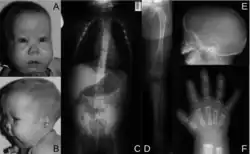

The ability of the Kozak sequence to optimize translation can result in novel initiation codons in the typically untranslated region of the 5′ (5′ UTR) end of the mRNA transcript. A G to A mutation was described by Bohlen et al. (2017) in a Kozak-like region in the SOX9 gene that created a new translation initiation codon in an out-of-frame open reading frame. The correct initiation codon was located in a region that did not match the Kozak consensus sequence as closely as the surrounding sequence of the new, upstream initiation site did, which resulted in reduced translation efficiency of functional SOX9 protein. The patient in whom this mutation was detected had developed acampomelic campomelic dysplasia, a developmental disorder that causes skeletal, reproductive and airway issues due to insufficient SOX9 expression.[32]